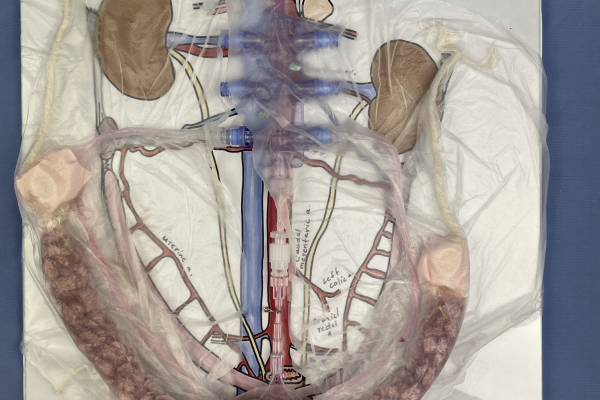

This model is used in an active learning activity for small animal anatomy. It is used to reinforce the anatomy and topography of the female reproductive tract in a clinically relevant context- an ovariohysterectomy (OHE)/spay surgical procedure.

Red fluid pushed by syringe through tubing mimics the collateral circulation servicing the uterus and ovaries in the cat and dog. String simulates the suspensory and round ligaments. Press’NSeal® secures the uterus, ovaries, vasculature, suspensory, and round ligaments within the broad ligament and secures it to the base in an anatomically correct position. Students apply plastic clamps to provide hemostasis at the ovarian pedicle and at the uterine body, as would be done in a spay procedure.

Ligatures can be applied and hemostasis checked when teaching more advanced clinical skills.